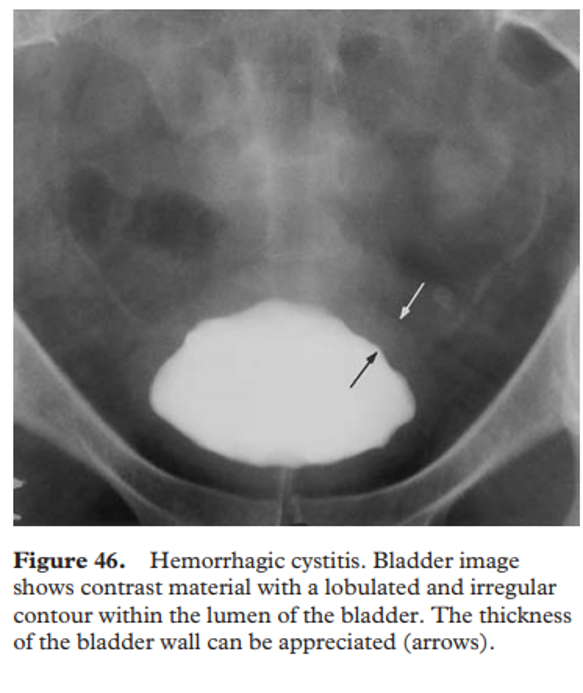

neurogenic bladder